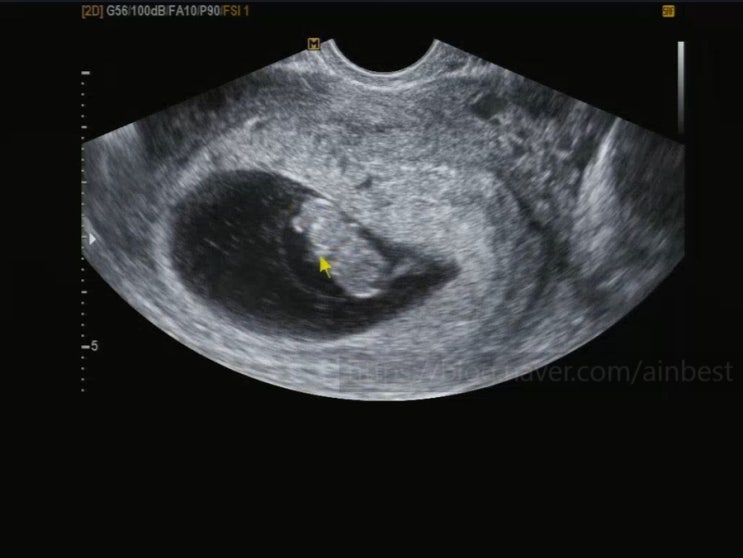

임신 22주. 베트남 나트랑 태교여행③. 깜란 퓨전리조트 수영장, 룸서비스, 담시장, 하이랜드커피, 육몽, 해피비치, 그리고 룸서비스ㅋ

임신22주. 베트남 나트랑으로 태교여행~ 2일차 일정 ((깜란 퓨전리조트 조식 - 퓨전리조트 수영장 - 룸서비...